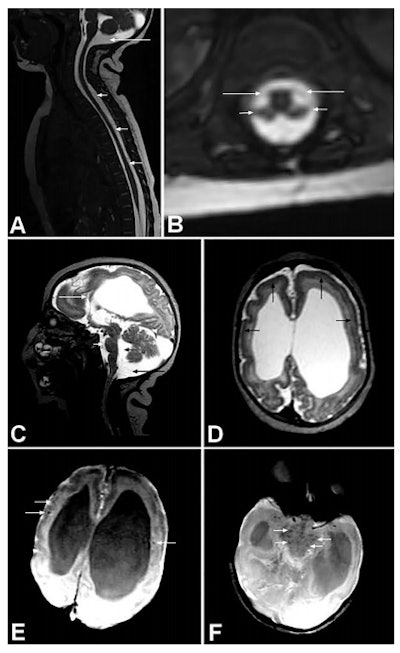

Spine and brain MRI of baby with arthrogryposis. A: Sagittal T2 weighted with fast imaging employing steady state acquisition (FIESTA) shows apparently reduced spinal cord thickness (short arrows) and mega cisterna magna (long arrow). B: Axial reconstruction of T2-weighted FIESTA shows reduction of medullary cone ventral roots (long arrows) compared with dorsal roots (short arrows). C: Sagittal T2-weighted image shows hypogenesis of corpus callosum (long white arrow), enlarged cisterna magna (long black arrow), enlarged fourth ventricle (short black arrow), and pons hypoplasia (short white arrow). D: Axial T2-weighted imaging shows pachygyria in frontal lobes (black arrows) and severe ventriculomegaly, mainly at posterior part of lateral ventricles. Axial susceptibility weighted image (E and F) show some hypointense, small dystrophic calcifications (white arrows) in junction between cortical and subcortical white matter (E) and in midbrain (F). All figures courtesy of the BMJ (2016;354:i3899, http://dx.doi.org/10.1136/bmj.i3899).Her group's article, published on 9 August by the BMJ, outlines the association between Zika virus infection in the womb and arthrogryposis, which causes joint deformities at birth, particularly in the arms and legs.